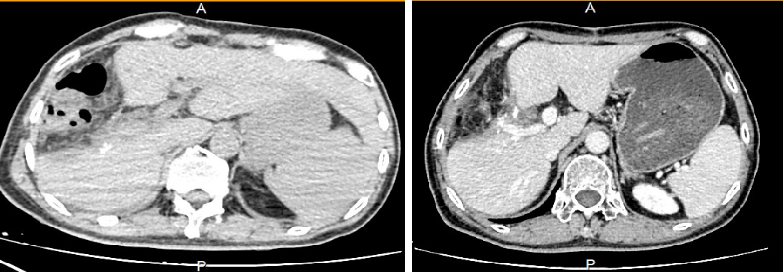

△出院前腹部CT平扫与术后1个月腹部CT增强